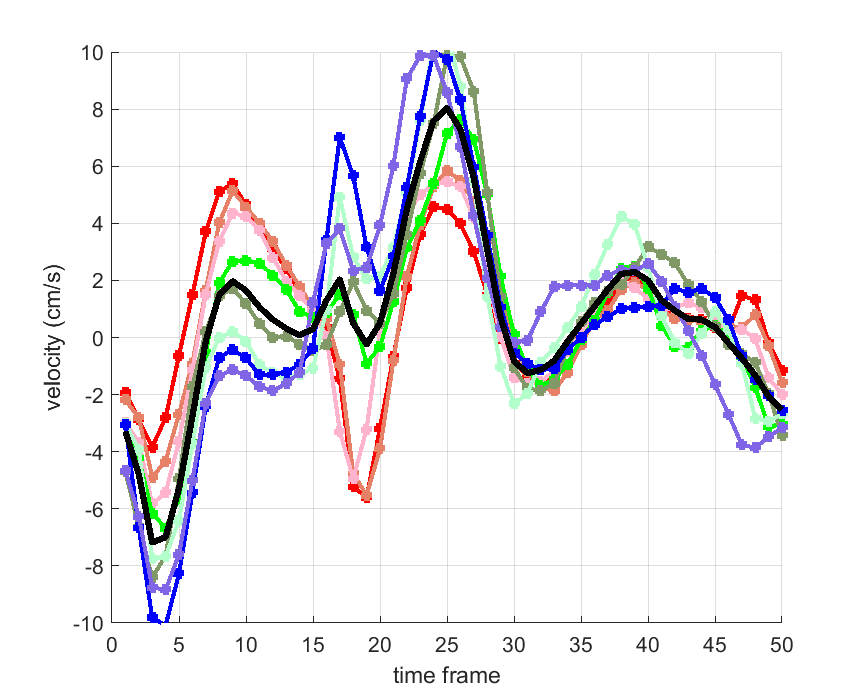

Time courses of the estimated translational component per subject, frame, slice and volume along the 3 velocity directions x, y and z are presented in Fig.6 - Fig.8.